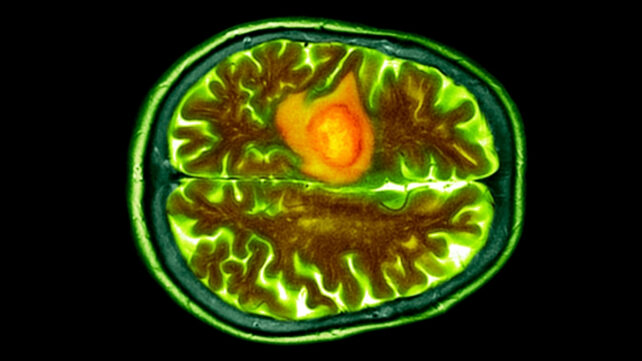

They transformed STING-activating molecules into spherical genetic material to maintain their stability for longer. To achieve this, the researchers wrapped the genetic material around a gold nanoparticle core.

The team then tested their medicine in mice with glioblastomas. They found that their gold-mounted genetic instructions successfully activated the STING pathway to inhibit tumor growth.

"With this research, we've shown that precisely engineered nanostructures, called spherical nucleic acids, can safely and effectively activate powerful immune pathways within the brain," says Stegh.